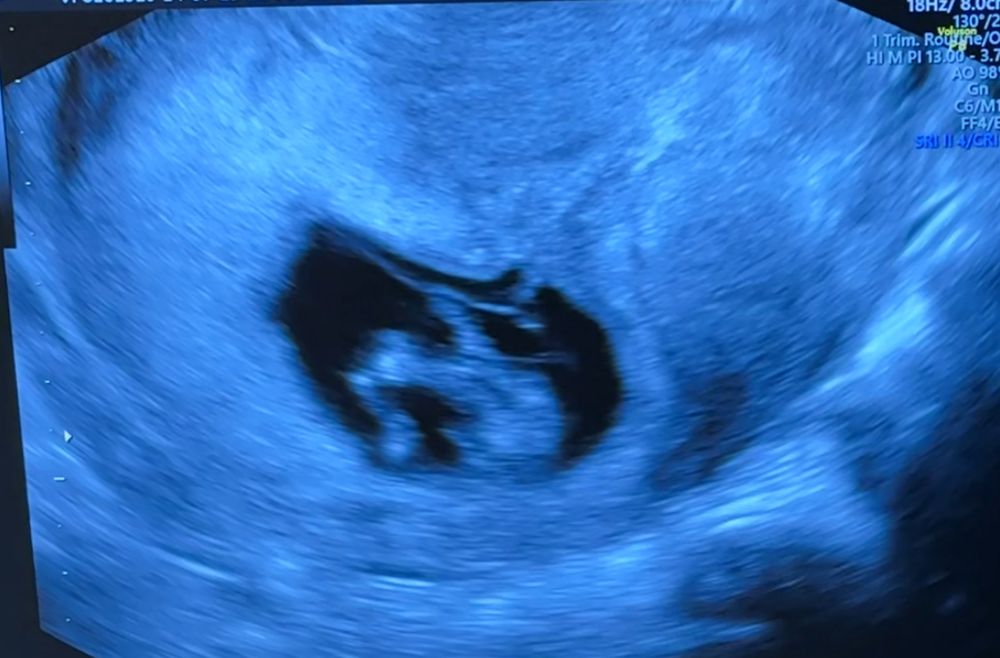

Пол ребенка в 12 нелель

Привет, девочки! 👋 Как вам кажется, какой пол у ребеночка? Расскажите, угадывали ли вам пол на первом скрининге? Мне в первую беременность в 12 недель сказали верно пол. 🙃

Мне не угадали, в 12+4 сказал врач уверенно что скорее всего мальчик, в 15+6 недель - девочка, так девочкой и осталась ☺️ я конечно не специалист, но как будто бы у вас мальчик 🤗

с такого ракурса не определить.

на таком сроке половых бугорок одинаковый у девочек и мальчиков.

нужно смотреть боковую проекцию и его угол относительно позвоночника

Если на первом фото малыш "попой сидит" то думаю мальчик. Мне первая гиня по сердцебиению сказала, что будет мальчик неделе на 15й, потом на 2м скирининге в 19 вроде недель пошла на узи и пол писали на бумажке для гендер тортика. И действительно мальчик

На таком сроке предполагают пол по половому бугорку, его в профиль видно. Тут ничего не видно.